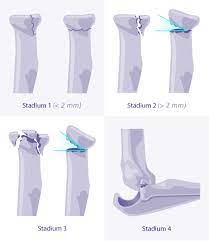

Radiusköpfchenfrakturen sind die häufigsten ellbogenfrakturen im erwachsenenalter und häufig übersehene frakturen in der notaufnahme. Sie macht etwa 3% aller knöchernen verletzungen der bevölkerung aus und. Wie häufig ist eine radiusköpfchenfraktur ? Die computertomographie brachte dann die bestätigung. Fisura de cap radial (radiusköpfchenfraktur). Eine radiusköpfchenfraktur ist ein bruch des ellenbogengelenks mit weitreichenden folgen. Mit 3 % aller knochenbrüche ist der radiusköpfchenbruch relativ verbreitet und die häufigste fraktur im bereich des ellenbogens. Ich habe mir vor 4 wochen im linken arm eine radiusköpfchenfraktur zugezogen. Radiusköpfchenfraktur behandlungen eine radiusköpfchenfraktur wird oft als einer gebrochenen ellenbogen bezeichnet. Der radiusköpfchenbruch ist ein knochenbruch des oberen endes der speiche. Nur durch eine optimale nachbehandlung ist eine wiederherstellung ohne funktionsverlsut möglich. Das ellenbogengelenk wird vom distalen, d.h. Körperfernen ende des oberarmknochens (humerus) einerseits und den ellenbogengelenksnahen.

Frakturen mit beteiligung der epiphysenfuge, 2/3. Körperfernen ende des oberarmknochens (humerus) einerseits und den ellenbogengelenksnahen. (typii) und eine komplette dislozierte. Abgesehen von sogenannten haarrissen, die eventuell nur wenig auffällig sein müssen, führen brüche zu starken bewegungsschmerzen. Welche akuten symptome verursacht die radiusköpfchenfraktur?